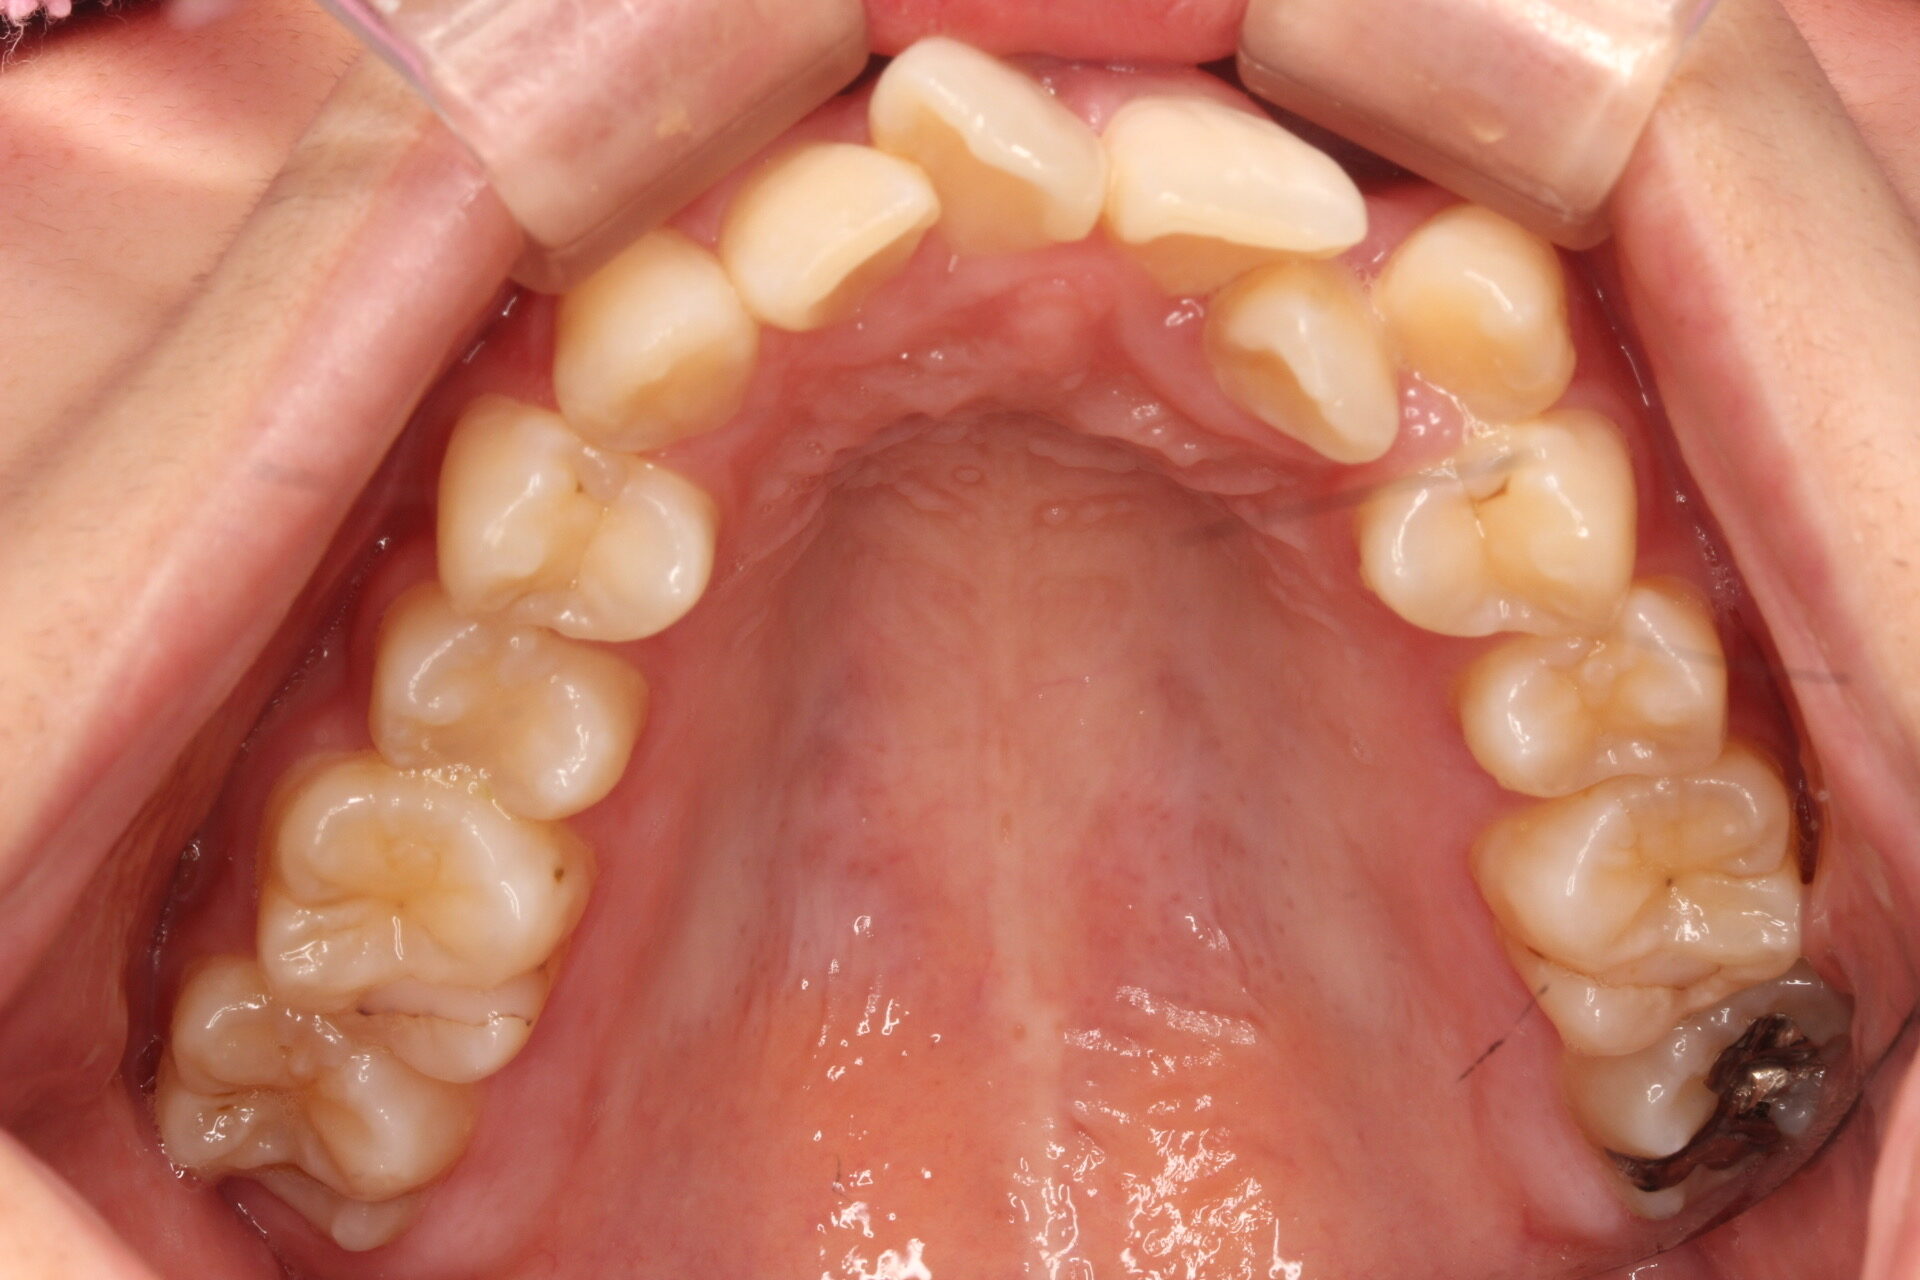

矯正術前:上顎

矯正術後:上顎